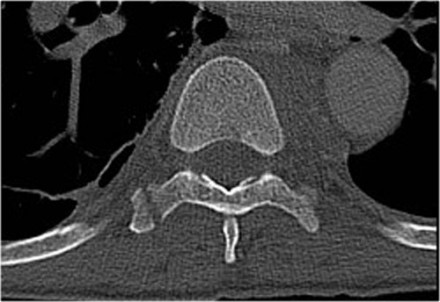

The images are of a patient with a typical bamboo spine as a result of ankylosing spondylitis.

After a fall on his back no fracture was seen on the x-rays.

However the CT shows a thin fracture line through the anterior side of the vertebral body and also through the spinous process.

Continue with the MR-images.